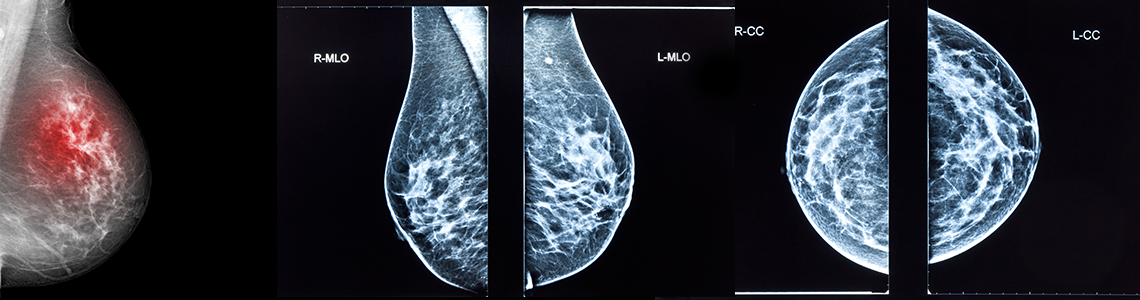

Mammographie, digitale Mammographie

Methode zur Früherkennung von Brustkrebs

• Mammographie

Scheuen Sie sich nicht uns auf eine individuelle Beratung anzusprechen! Auf Wunsch erhalten Sie Aufklärungsbroschüren. Ab dem 40. Lebensjahr 1x pro Jahr Mammographie und Brustultraschall senkt die Sterblichkeit durch Brustkrebs um 25-30%.*

Mammographie